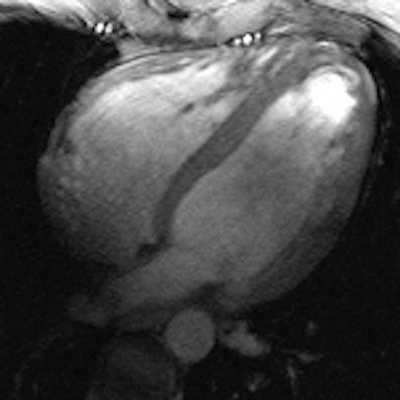

All these efforts culminated in images of the beating heart with a spatial resolution that is by a factor of five superior to that routinely available at 1.5 tesla, and which might come close to turning a 10-megapixel digital camera into a 50-megapixel digital camera. These improvements offer detailed insights into cardiac anatomy and allow accurate delineation of myocardial borders, a feature that is essential for cardiac chamber quantification.

Cine images (left: four-chamber view, middle: short-axis view, right: two-chamber view) of the beating heart acquired with a novel 16-channel transmit/receive radiofrequency coil array at 7.0 tesla with an in-plane resolution of 1 x 1 mm2 and a slice thickness of 4 mm. Images courtesy of Dr. Thoralf Niendorf.The novel technology tailored for cardiac MRI together with the quality of the anatomical and functional images have created excitement among the international imaging community during the ISMRM meeting, which ran a special session on ultrahigh-field CMR. The first clinical results and experiences are very much heartening and are the driving force for broader clinical studies.